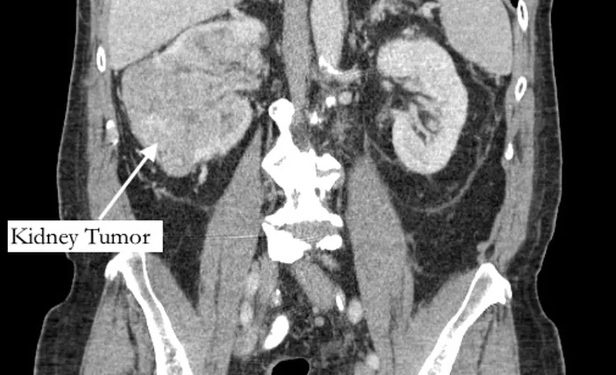

Segundo o jornal “New York Post”, Richard Bernstein, 42, sentia a dor havia cinco anos, e pensava que se tratava de uma fratura, mas recebeu o diagnóstico de grande tumor no rim e de um trombo tumoral, um tumor que se estende até um vaso sanguíneo.

O exame, encaminhado a um urologista, identificou ainda um trombo (coágulo no sangue) que cresceu através da veia renal e preenchia a veia cava, que drena sangue para o coração, e tinha 99% das artérias da coronária bloqueadas, além do fígado quase entrando em falência.

O paciente passou então por uma cirurgia de urgência para remover o tumor.

Após 12 horas de uma cirurgia complexa e casada entre médicos de diferentes especialidades, o tumor e o trombo foram retirados e uma ponte de safena foi realizada.